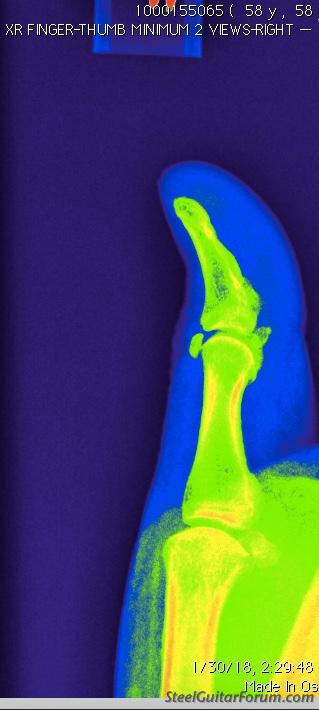

Not the base of my thumb, but the first knuckle and apparently not arthritis. It looks like I have a kneecap on my thumb and it hurts like hell. Diclofenac helps, but this might require some work. My doctor says it's essentially "unremarkable"....

Image

Ouch.